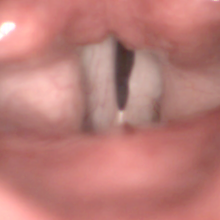

analýza záznamů

z vysokorychlostní kamery ...

LHSV

(Laryngeal High-Speed Video Endoscopy)

funkční a popisná vyšetřovací metoda, analýza dynamiky a kinematiky hlasivek

princip metody:

» videosekvence

se záznamem kmitání hlasivek

» 4000

snímků/s, 512 x 512, resp. 256 x 256 obrazových bodů/snímek

» zpracování

jednotlivých snímků, automatická detekce štěrbiny

» výpočet

a analýza parametrů